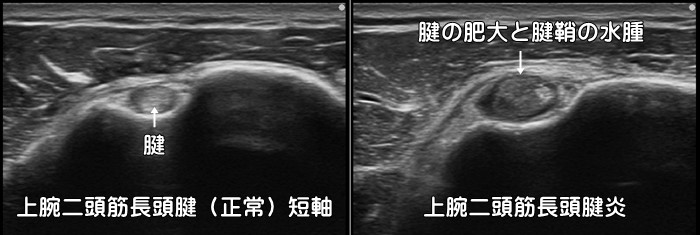

上腕二頭筋長頭腱炎

肩の前方または外側の長引く痛みの原因として上腕二頭筋長頭腱炎・腱鞘炎があります。リレーのバトンを受け取るように後ろへ腕を伸ばすと痛みが増強します。肩だけではなく、上腕の外側や時に前腕から手首にまで痛みが出現します。肩の腱鞘炎ですのでいわゆる使い過ぎ症候群です。炎症反応の動画はこちらで確認できます。